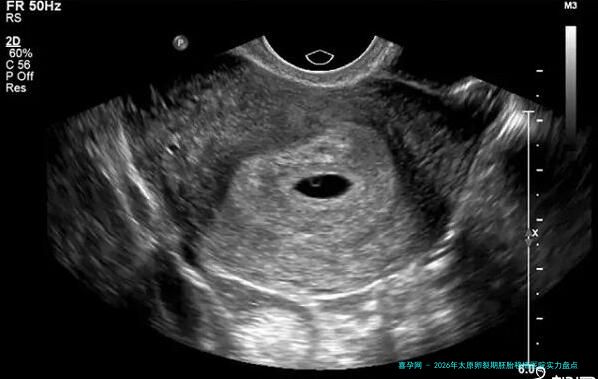

卵裂期,通常指受孕后第2到3天的胚胎。这个阶段的胚胎恰好在快速细胞决裂时期,其形态、细胞体数目和碎片率是评介其发育潜力的重要标准。优质的卵裂期胚胎是后续成功着床的丰厚基础。实践室的胚胎培养环境、技术人员的操作水平以及胚胎学专家的评介本事,直接决计了可用胚胎的质量。